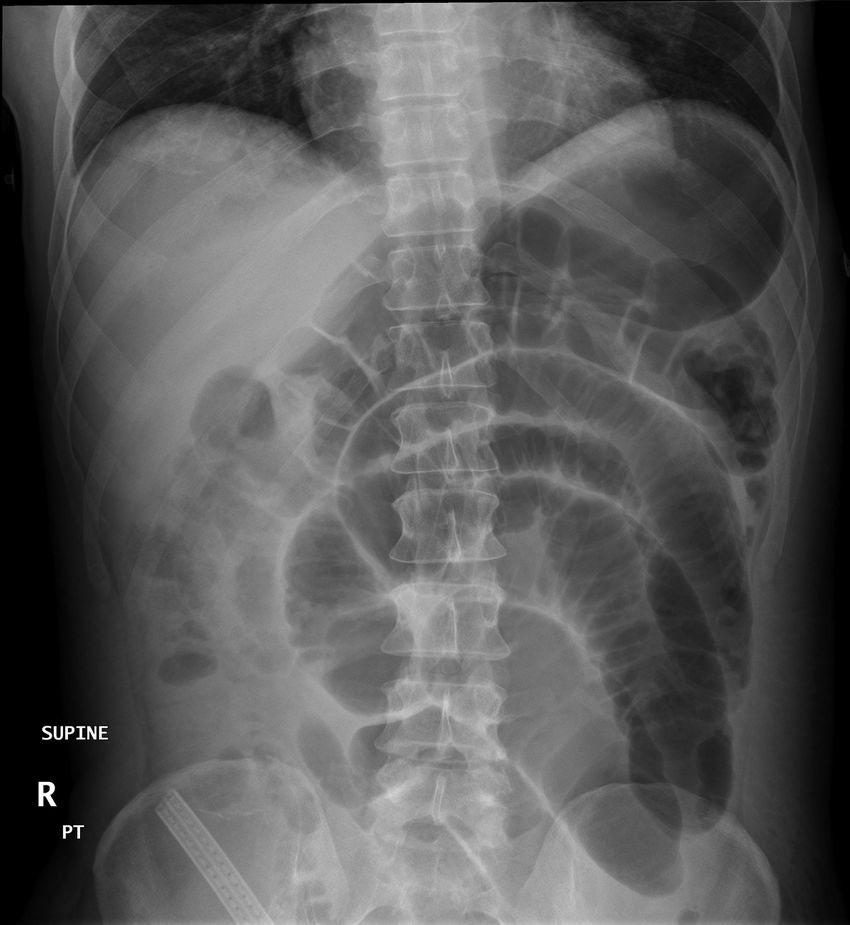

The initial investigation of choice for suspected case of bowel obstruction is supine x-ray. The level of obstruction can be demonstrated mostly on x-ray. In cases where level of obstruction is not defined, CT scan is the diagnostic modality of choice. Dilated loops are easily demonstrated in case of bowel obstruction. Gas-fluid levels > 2.5 cm are indicated of bowel obstruction. Reference: Bailey and Love's Short Practice of Surgery Image via: https://www.researchgate.net/publication/49764047_Evaluation_and_Management_of_Intestinal_Obstruction/figures?lo=1